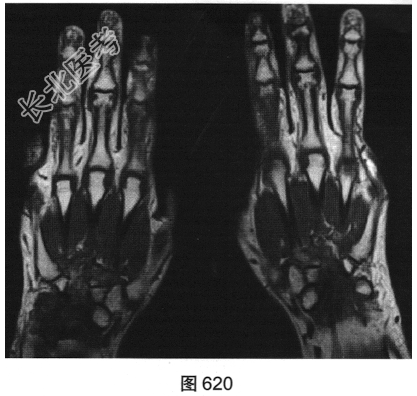

- 简答题2、患者行双手X线及MRI检查,见图619~图622。请问X线平片及MRI图像有哪些阳性表现?